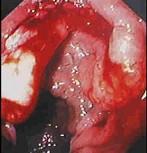

问题 男性,50岁。消瘦、乏力半年,间断性上腹胀痛伴黑便2周。发育正常,体形消瘦,贫血外貌,皮肤无黄染,腹平坦,腹肌软,上腹偏右压痛,肝脾肋缘下未触及。低张气钡双重造影示十二指肠降段肠壁僵硬,蠕动消失,肠腔不规则狭窄。胃镜检查如下图,下列正确的是 ( )

选项 A.十二指肠腺癌可能大 B.卓-艾综合征可能大 C.该病可导致黄疸 D.该病以中年人多见 E.该病首选手术治疗,无手术指征者可考虑放、化疗

答案 ACDE